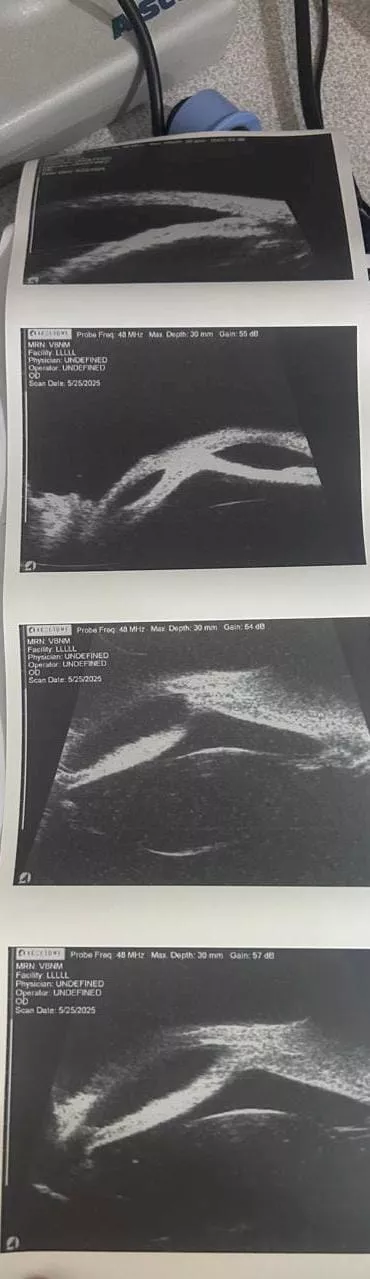

أعلن االدكتور حموده الجزار، وكيل وزارة الصحة بمحافظة الدقهلية، تشغيل جهاز UBM – Ultrasound Biomicroscopy داخل مستشفى رمد المنصورة، مؤكدًا أن تشغيل الجهاز يُعد نقلة نوعية في مجال التشخيص الدقيق لأمراض العيون، بما يسهم في الارتقاء بجودة الخدمات الطبية المقدمة للمرضى.

وأوضح وكيل الوزارة، أن الجهاز يُمكّن الأطباء من فحص وتشخيص أدق تفاصيل العين، والتعرف على أورام العين الأمامية، وتقييم حالات المياه الزرقاء (الجلوكوما)، وتشخيص الأمراض الناتجة عن النمو غير المكتمل للمنطقة الأمامية للعين، بالإضافة إلى إجراء الفحوصات اللازمة قبل زراعة القرنية، مؤكدًا أن هذه الخطوة تأتي في إطار حرص مديرية الصحة على توفير أحدث التقنيات لخدمة أهالي الدقهلية والمرضى من المحافظات المجاورة.

من جانبه، أكد الدكتور أحمد حسان، مدير مستشفى رمد المنصورة، أن الجهاز بدأ بالفعل في استقبال الحالات داخل وحدة الفحوصات بالمستشفى، تحت إشراف نخبة من الأطباء المتخصصين في طب العيون، من بينهم الدكتور أحمد سليم، والدكتور إسلام عبد الهادي، والدكتورة رنوي مختار، والدكتورة أماني محمد علي، والدكتورة ريم غازي، مشيرًا إلى أن المستشفى يستقبل جميع الحالات المحولة من مختلف المراكز والمستشفيات بالمحافظة.